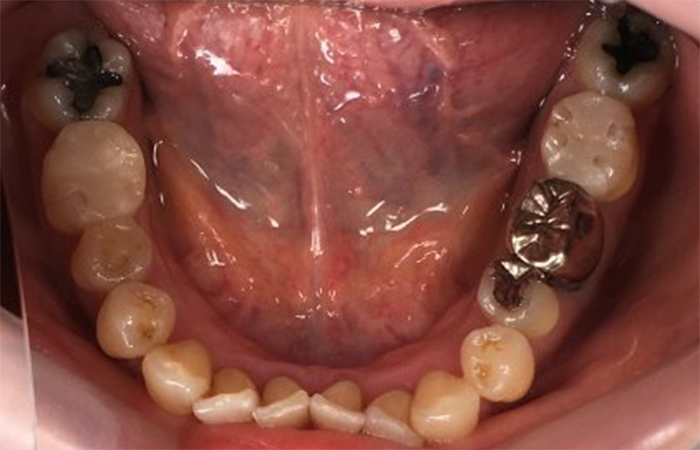

治療前 ![]() |

奥歯で噛んだ際の違和感があり来院されました。あわせて、既存の金属修復物が目立つことによる審美的なストレスがあり、さらに金属アレルギーへの不安も感じていらっしゃいました。 |

強い咬合力による歯牙破折が認められ、その破折部から細菌が侵入したことによるう蝕が確認されました。また、既存のメタル修復物により、見た目の問題(審美障害)だけでなく、金属材料による身体への影響も懸念される状態でした。 |